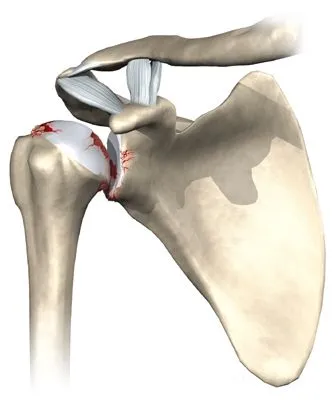

- au mauvais fonctionnement ou à la rupture des tendons de la coiffe des rotateurs. On parle alors d'omathrose excentrée. Dans ce cas la prothèse qui sera mise en place sera une prothèse inversée qui remplacera également la fonction des tendons de la coiffe des rotateurs.

Aspect radiographique d'une omarthrose primitive

Arthroscanner d'une omarthrose secondaire secondaire à une lésion de la coiffe des rotateurs.